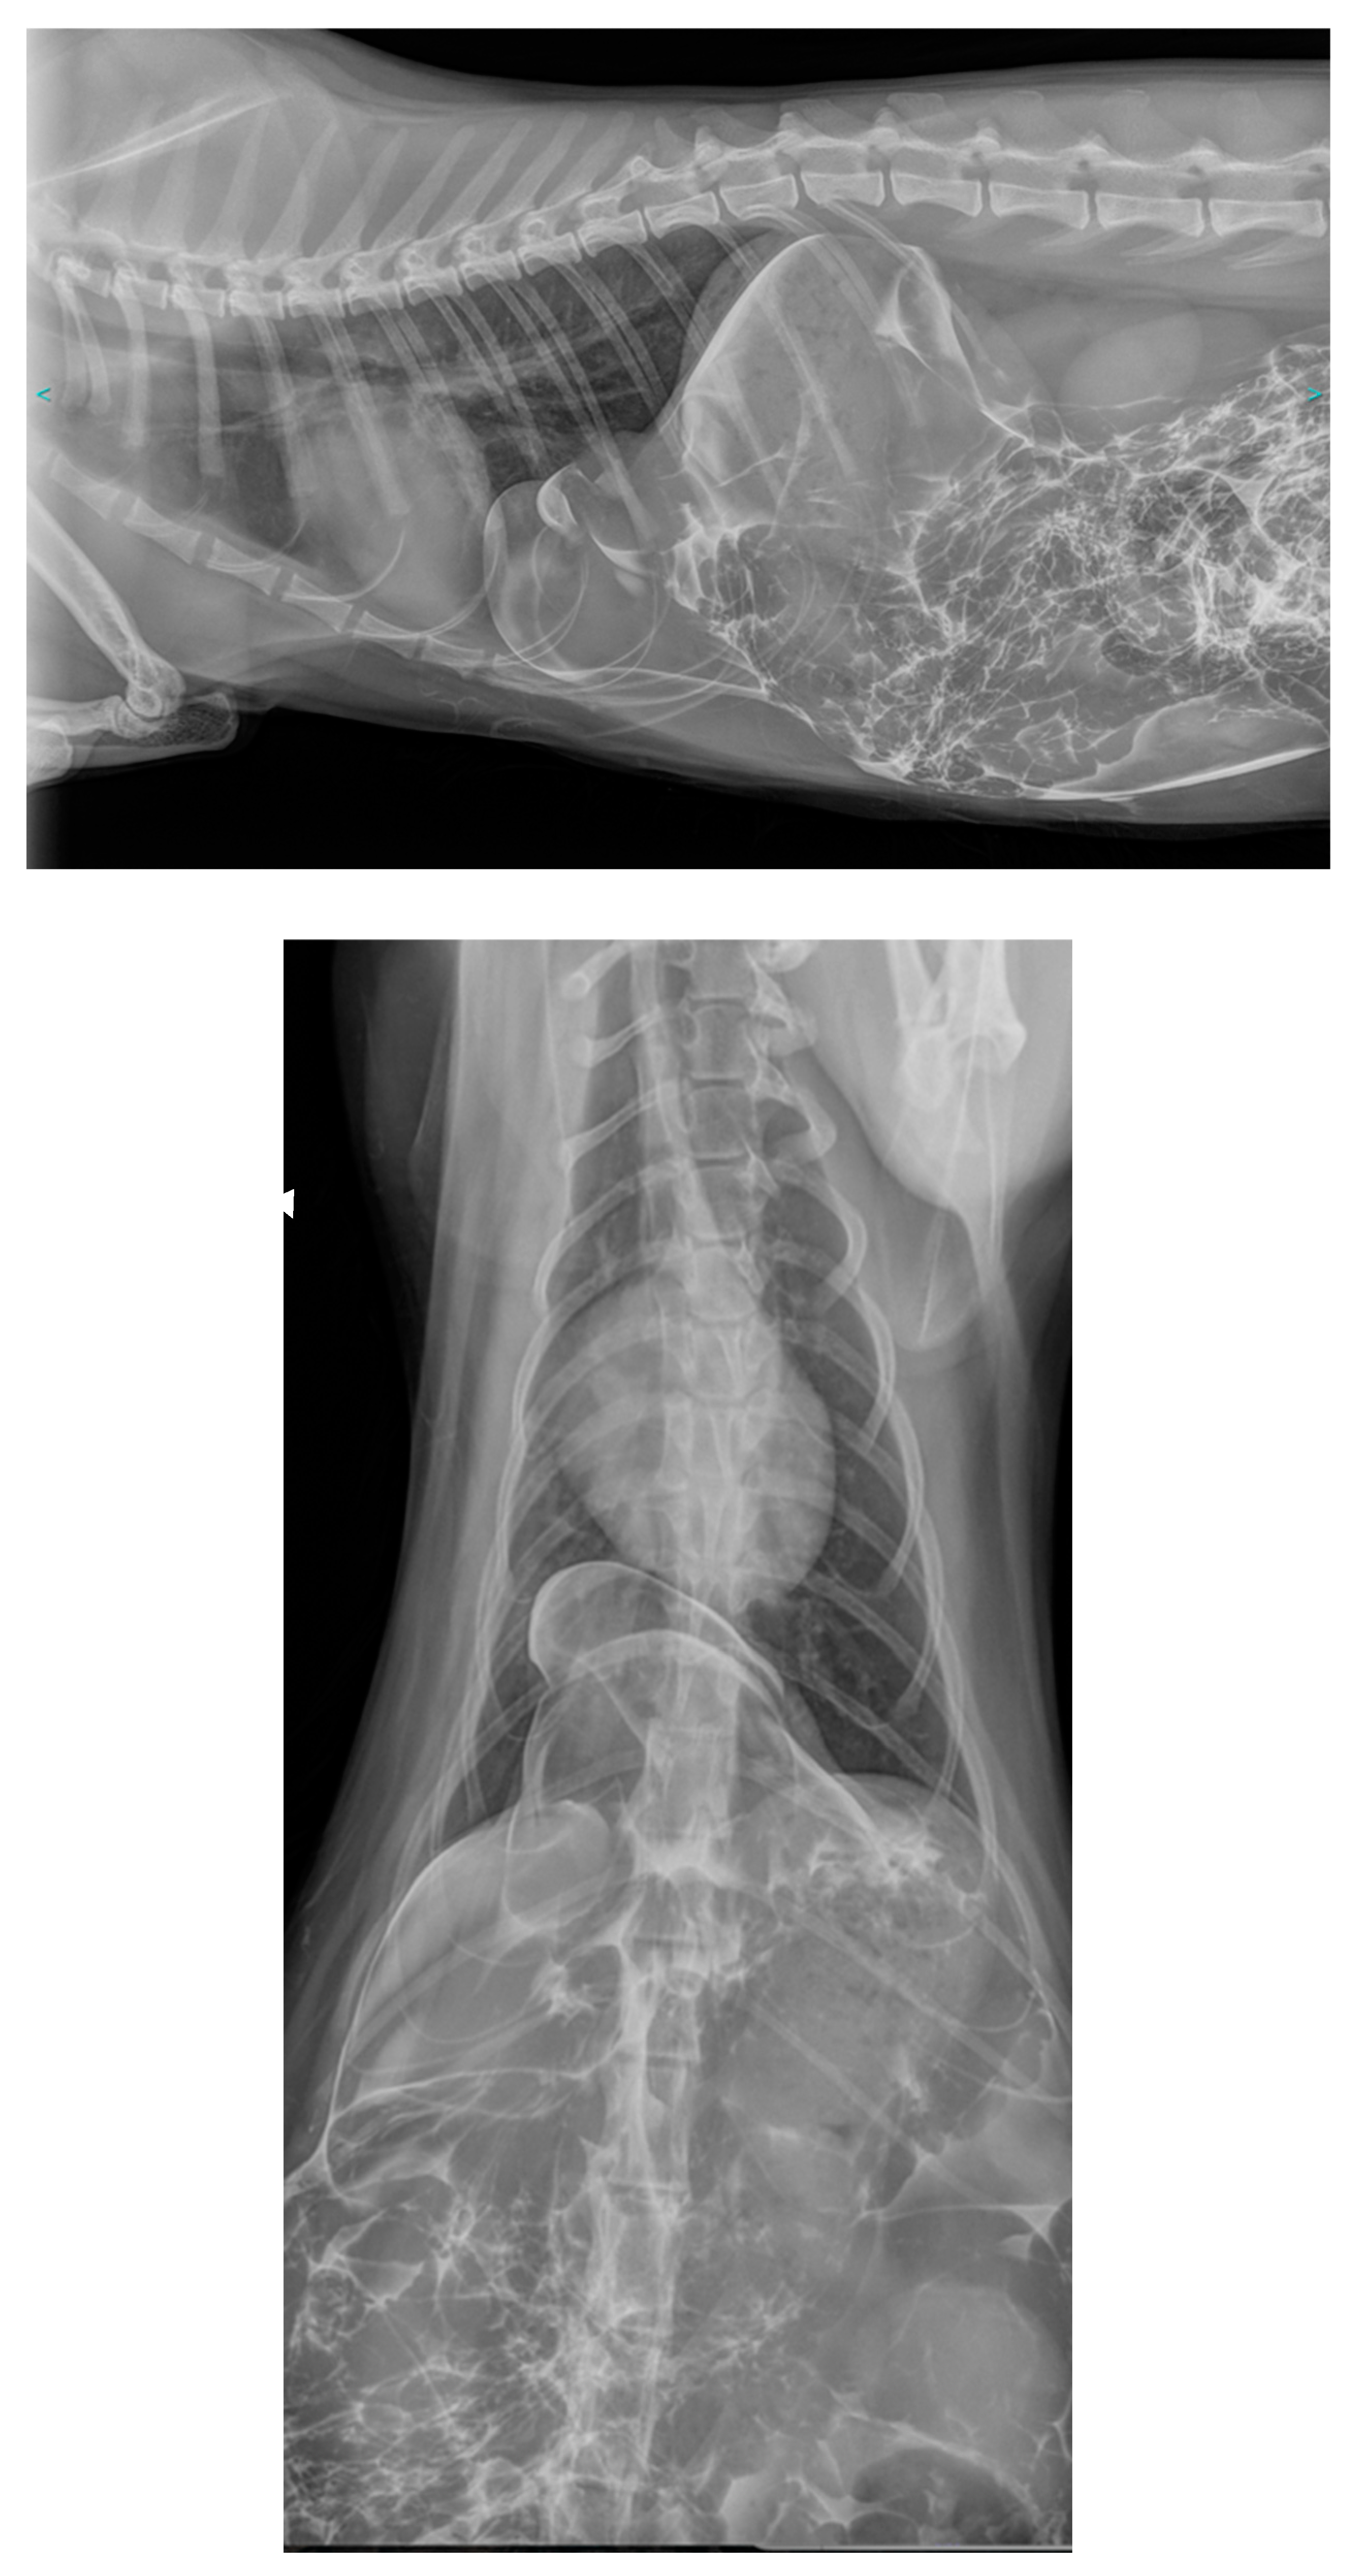

In the veterinary literature, the type of true diaphragmatic hernia is not specified by the authors. However, there are different names used in humans depending on the location. Vosges et al. [11,15] and Carriou et al. [11,15] draw a parallel between the “true diaphragmatic hernia” described in cats and the “Bochdalek hernia” described in humans. Indeed, Bochdalek hernias represent 95% of congenital diaphragmatic hernias in humans, but Bochdalek hernia is a posterolateral hernia [30] whereas the hernias described by these authors were ventral (anterior) .

In humans, there are two types of congenital diaphragmatic hernias linked to incomplete fusion of the diaphragm: hernias located in the posterolateral region, right or left, called “Bochdalek hernias” (first described in 1848 by Vincent Alexander Bochdalek) and hernias located in the anterior and retrosternal region, called “Morgagni hernias” on the right (first described by Giovanni Battista Morgagni in 1769) or “Larrey hernias” on the left (attributed - wrongly - to Dominique Jean Larrey in 1812). Some authors do not distinguish between right and left anterior hernias and describe all anterior congenital hernias as “Morgagni hernia” [31]; 90% of Morgagni hernias occur on the right side due to the pericardial attachments to the diaphragm that provide protection and support to the left side [32].

In the current case, the diaphragmatic defect, being radial, ventral, and to the right, corresponds to the right anterolateral hernia found in humans, known as “Morgagni hernia”. To the best of our knowledge, this is the first instance where the term “Morgagni hernia” is employed in veterinary medicine to describe this congenital anomaly. Nevertheless, six cases previously reported in cats [11,12,15,16,19,20] - including the cases by Vosges et al. and Carriou et al. - along with three cases in dogs [21,22] appear to be consistent with a Morgagni hernia, as the radiological images are directly comparable to those of the current case.

Only the case described by Green et al. [13], which reports radiopaque structures ventrally and in the left hemithorax, seems to align with the “Larrey hernia” described in humans. Among the 4 cases of true diaphragmatic hernias reported in dogs, only the case of Devereux et al. [23] concerns a small discontinuity of the ventral left diaphragm and can therefore be considered as a Larrey hernia.

In the three cases reported by Mann et al. [10], White et al. [14], and Rose et al. [18], the authors note a radiopaque soft-tissue mass in the midportion of the diaphragmatic crus : unlike Morgagni or Larrey hernias, the mass is not ventrally positioned. This location seems to correspond more with a “caval foramen hernia”, even though the first two cases mention the presence of a hernial sac, which is unusual in humans.

Thus, all true diaphragmatic hernias in cats are Morgagni hernias in the broad sense, that is, either right or left; as far as we are aware, there have been no reports of hernias in cats that correspond to the Bochdalek hernia seen in humans (posterolateral) (Figure 4). On the contrary in human, Morgagni hernias, in a general sense, account for only 2 to 5% of congenital diaphragmatic hernias and Bochdalek hernias represent at least 95% of congenital diaphragmatic hernias [31,32].

Figure 4. Location of diaphragmatic hernias in cats.